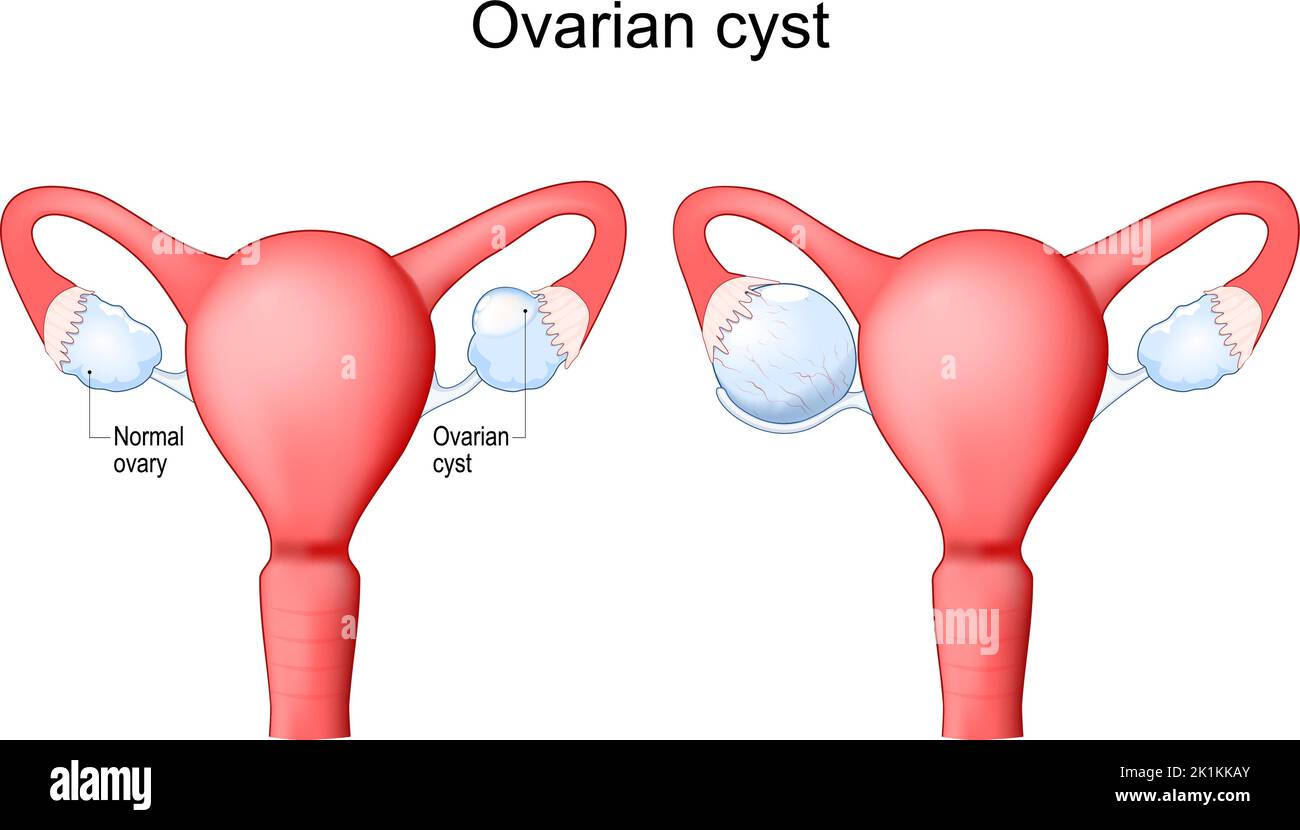

Kyste ovarien Utérus humain avec sac rempli de liquide à l'intérieur de l'ovaire. Système reproducteur féminin. Illustration vectorielle Illustration de Vecteurhttps://www.alamyimages.fr/image-license-details/?v=1https://www.alamyimages.fr/kyste-ovarien-uterus-humain-avec-sac-rempli-de-liquide-a-l-interieur-de-l-ovaire-systeme-reproducteur-feminin-illustration-vectorielle-image482937251.html

Kyste ovarien Utérus humain avec sac rempli de liquide à l'intérieur de l'ovaire. Système reproducteur féminin. Illustration vectorielle Illustration de Vecteurhttps://www.alamyimages.fr/image-license-details/?v=1https://www.alamyimages.fr/kyste-ovarien-uterus-humain-avec-sac-rempli-de-liquide-a-l-interieur-de-l-ovaire-systeme-reproducteur-feminin-illustration-vectorielle-image482937251.htmlRF2K1KKAY–Kyste ovarien Utérus humain avec sac rempli de liquide à l'intérieur de l'ovaire. Système reproducteur féminin. Illustration vectorielle